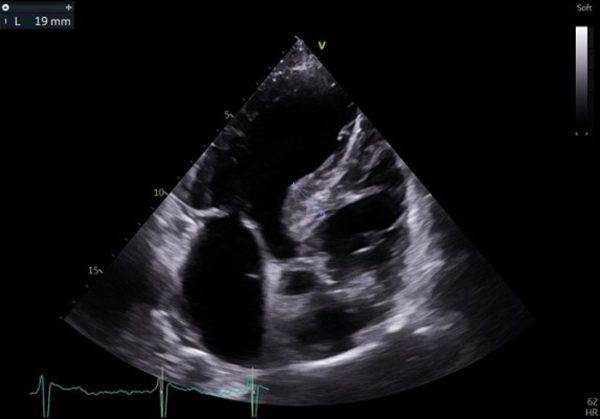

ETT

Figure 2

Vidéo 1

Figure 3

Figure 4

Conclusion de l'ETT :

- CMH asymétrique à prédominance septale (épaisseur maximale 19mm); FEVG préservée et cinétique homogène

- Accélération sous aortique, sans obstruction significative de repos; y compris après Valsalva

- Absence de valvulopathie significative, OG dilatée (56mL/m2); aorte non dilatée

- VD non dilaté, non hypertrophié, de bonne fonction systolique